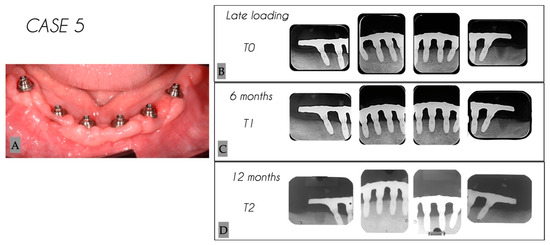

| 5 | Male | 53 | Mandible | 6 |

| Case No. | Tooth No. | Initial MBL (mm) | MBL 6 Months (mm) | MBL 12 Months (mm) | KM 6 Months (mm) | KM 12 Months (mm) |

|---|---|---|---|---|---|---|

| 5 | 46 | 1.30 | 1.92 | 2.30 | 4 | 4 |

| 5 | 44 | 1.06 | 1.25 | 2.27 | 3 | 3 |

| 5 | 42 | 0.63 | 1.09 | 2.29 | 5 | 5 |

| 5 | 32 | 0.71 | 1.44 | 1.61 | 4 | 4 |

| 5 | 34 | 1.25 | 2.03 | 2.52 | 4 | 4 |

| 5 | 36 | 0.86 | 1.24 | 2.48 | 2 | 2 |

| Mean | 0.97 | 1.50 | 2.25 | 3.7 | 3.7 | |